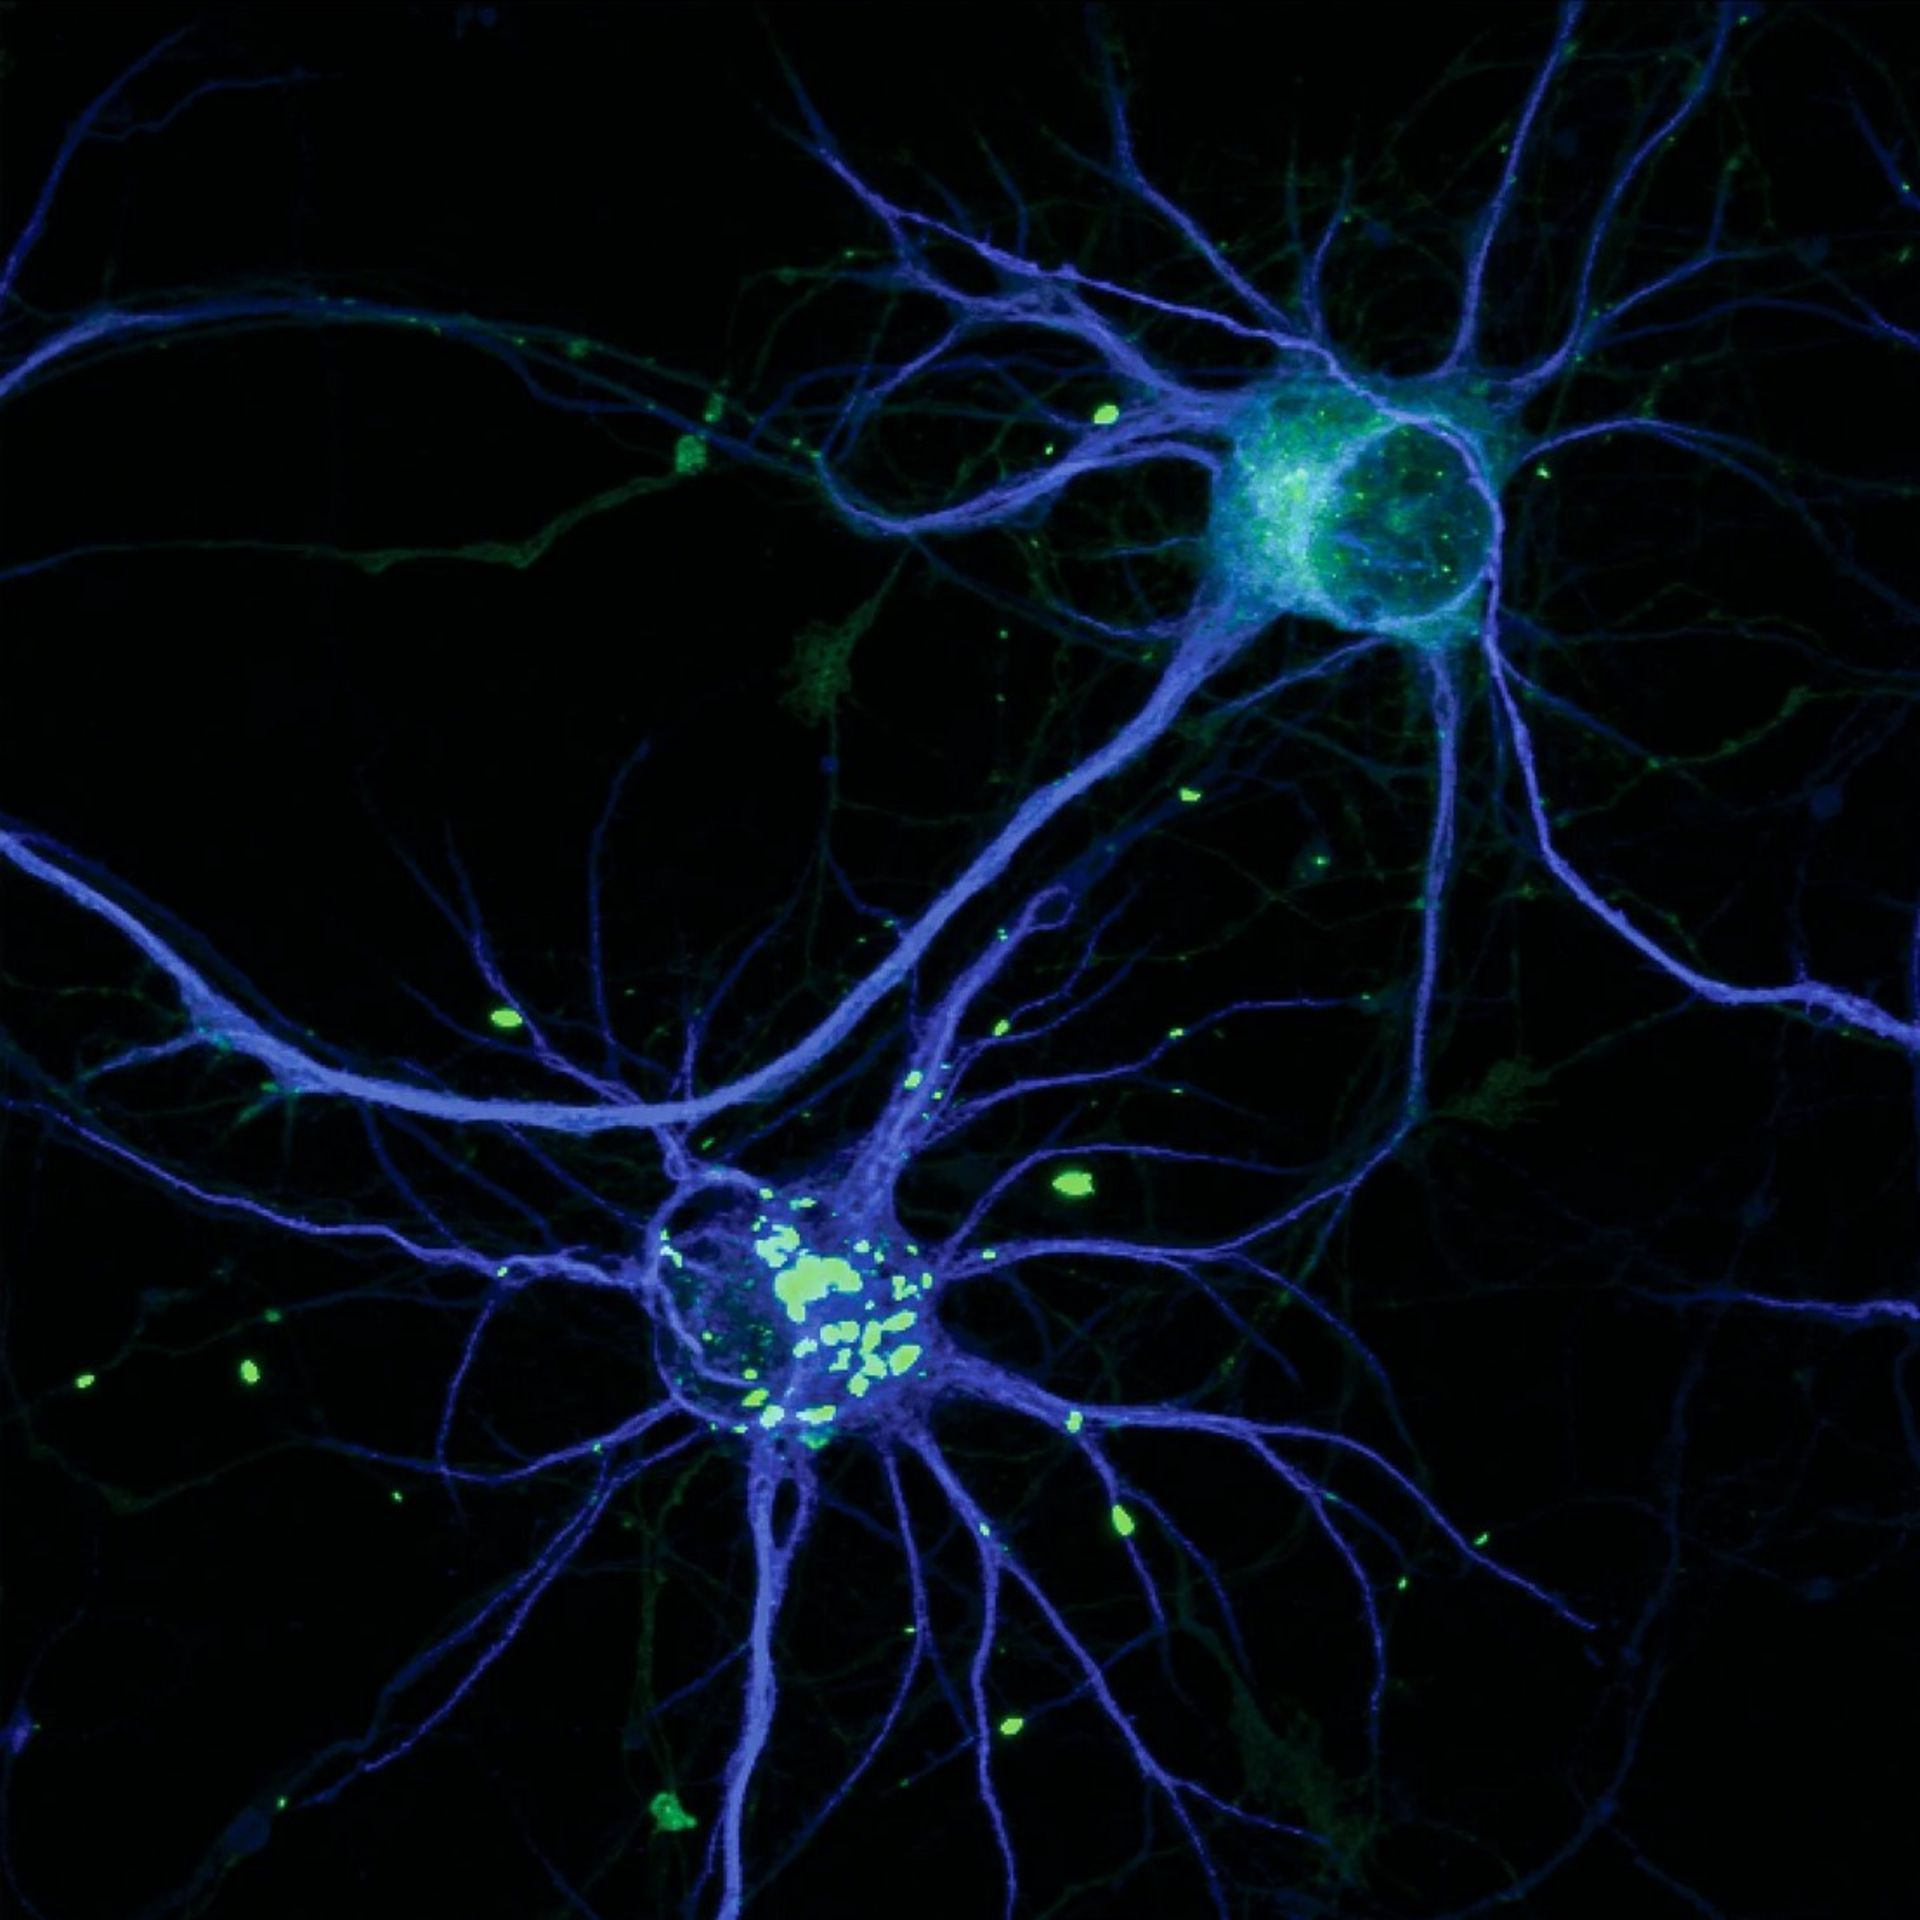

نسخه‌ای سمی از پروتئین HTT عامل بیماری هانتینگتون منجر به ایجاد توده‌هایی می‌شود که با رنگ سبز روشن روی تصویر مشهود است